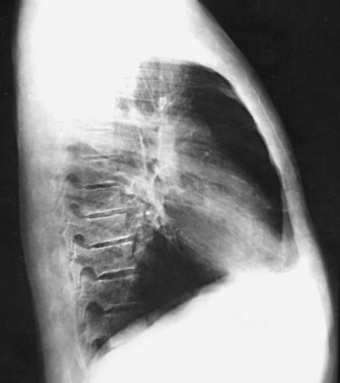

Structures shown: The preliminary left lateral chest position is used to show the heart, the aorta, and left-sided pulmonary lesions (Figs. 10-37 and 10-38). The right lateral chest position is used to show right-sided pulmonary lesions (Fig. 10-39). These lateral projections are employed extensively to show the interlobar fissures, to differentiate the lobes, and to localize pulmonary lesions.

Fig. 10-38 A, Left lateral chest. B, Right lateral chest on same patient as in A. Note the size of the heart shadows.